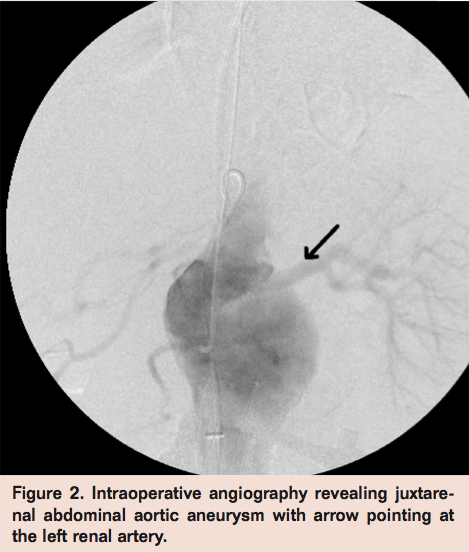

An 84-year-old female presented to the emergency department with acute onset of severe abdominal and back pain of 2 days duration. Her past medical history was significant for hyperlipidemia, coronary artery disease with coronary artery bypass graft 20 years prior, renal artery stenosis treated with left renal artery stenting, first-degree atrioventricular heart block, gastroesophageal reflux disease, and hypothyroidism. Her social history was significant for 50 pack years of smoking. Her vital signs were within normal limits and her physical exam was significant for lower abdominal tenderness and a pulsatile abdominal mass. Her computed tomography angiogram revealed a 5.4 cm by 5.1 cm pararenal AAA involving the origin of the previously stented left renal artery (Figure 1). Given the patient’s comorbid conditions, including coronary artery disease, atrioventricular block, and possibly poor pulmonary reserve function due to her chronic history of smoking (pulmonary function tests were not obtained), the decision was made to proceed with endovascular aortic aneurysm repair using a chimney graft with a snorkel in the left renal artery.